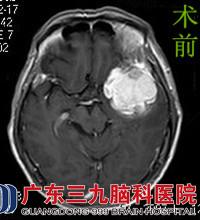

原来近日的各种症状竟是肿瘤所致。为了进一步治疗,天淑来到广东三九脑科医院综合神经外科。行头颅MR检查提示左侧额颞部示不规则团块状异常信号,大小约48.1mm×46.8mm×47.4mm。完善相关检查后,由鲁明主任主刀,在全麻下行左侧翼点入路蝶骨嵴脑膜瘤切除术,术中见肿瘤位于颞叶,质软,血供丰富,予镜下行肿瘤全切,手术顺利结束。术后天叔经治疗护理,康复出院。术后病理结果:过渡型脑膜瘤。